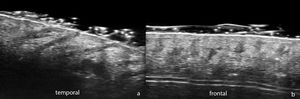

En el ámbito de la tricología, se describe ecográficamente a los folículos pilosos normales como bandas hipoecogénicas oblicuas en la dermis que, en fase anágena, se localizan en la dermis profunda o incluso en la hipodermis superior, mientras que en fase telógena se restringen a la dermis superior (fig. 1). En el cuero cabelludo los tallos pilosos se informan como estructuras hiperecogénicas predominantemente trilaminares con un complejo cutícula-corteza externo y una médula interna2,6. Al comparar la EAF con tricoscopia, se ha reportado que el número de unidades foliculares no difiere de forma significativa y solo su ancho es mayor con las mediciones ecográficas7. En la EUAF se observan los tractos pilosos en el interior de los folículos antes de emerger a la superficie2,5.